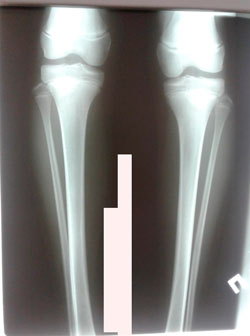

Плоскостопие тяжёлой степени.

IMG_2487-16-04-19-07-27.JPG

IMG_2486-16-04-19-07-27.JPG